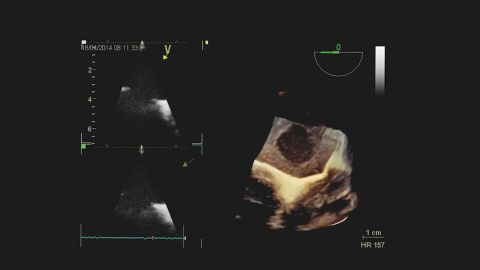

Wideo Echokardiografia. Przypadek 2

prof. dr hab. n. med. Piotr LipiecPacjent z ostrą dusznością i hipotonią, bez wcześniejszego wywiadu chorób układu krążenia.